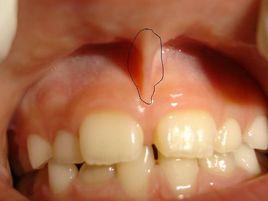

唇系帶的位置處於中切牙之間的唇側牙齦與牙槽黏膜交界處。其在胚胎時期相當粗大,絕大部分嬰兒在出生後會漸趨退縮。唇系帶延長的適用人群主要有兩大類,唇系帶過短者及嬰幼兒。唇系帶過短也就是出生後唇系帶不退縮且在牙床門之間附著過低,引起上門牙之間縫隙過寬。

唇系帶過短會影響嬰兒日後的發音,對於唇系帶過短的情況,可以通過唇系帶延長手術來進行矯正。由於唇系帶的正常發育應該是在嬰兒出生以後,所以對唇系帶異常的矯正也在是在嬰兒時期進行,以保證唇系帶能夠隨著嬰兒的成長逐漸發育成正常情況。採用唇系帶延長手術縫合後的唇系帶變化很小,一般不會影響發音,但一定要到正規醫院進行諮詢,手術前後都一定要聽從醫生的吩咐做好準備護理工作,以求達到最好和最安全的手術效果。

唇系帶延長術唇系帶延長術是通過手術的方法在唇系帶兩側做V字形切開,並進行口唇內側黏膜與牙槽骨側創面對位縫合,最終形成新的、到達正常長度的唇系帶。其具體操作步驟如下: